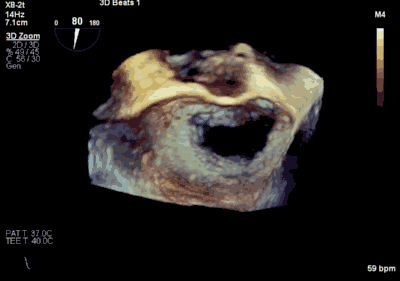

患者为66岁老年男性,4个月余前因“急性心肌梗死合并二尖瓣后叶腱索断裂”出现心源性休克,在IABP支持下仍反复发作左心心力衰竭,经过急诊血运重建联合优化药物治疗后症状好转,但术后多次发作严重左心心力衰竭,超声心动图评估二尖瓣反流急性增加至极重度,左房、左室显著扩大。此次主诉“反复胸闷、气促4月余”入院。诊断:心脏瓣膜病 二尖瓣脱垂伴重度关闭不全 二尖瓣后叶腱索断裂 心功能IV级(NYHA分级) 。术前经胸超声心动图示:全心扩大,二尖瓣后叶脱垂、腱索断裂合并重度关闭不全(DMR 4+)。心脏测值:LA 45mm LVD 55mm EF% 61% PASP 82mmHg。经食管超声心动图示:二尖瓣环左右径33mm,反流束缩流颈宽度为5.5mm,EROA 0.67cm2(PISA),舒张期二尖瓣口平均跨瓣压差5mmHg。

▲ 术前超声检查显示重度二尖瓣反流